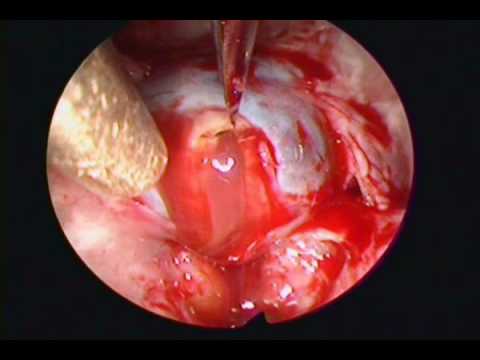

Tętniak tętnicy łączącej tylnej

Doktor Pakzaban prezentuje mikrochirurgiczny zabieg klipsowania tętniaka tętnicy łączącej tylnej.